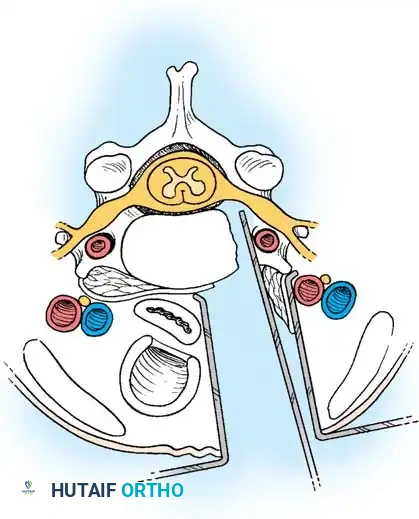

Current Standard of Care: Anterior Cervical Discectomy and Fusion (ACDF) is the procedure of choice when the disc is approached anteriorly. Fusion prevents disc space collapse, maintains foraminal height, prevents painful abnormal motion, and restores cervical lordosis. Conversely, posterior cervical foraminotomy is the procedure of choice for isolated, laterally located soft disc fragments where central decompression is not required.

The anterior approach utilizes the avascular plane between the visceral neuraxis (trachea/esophagus) and the vascular neuraxis (carotid sheath).

Step 1: Exposure and Retraction

Following a transverse incision within a natural skin crease (usually left-sided to protect the recurrent laryngeal nerve, which has a more predictable course on the left), the platysma is divided. The deep cervical fascia is incised anterior to the sternocleidomastoid. Blunt dissection separates the carotid sheath laterally from the trachea and esophagus medially. The prevertebral fascia is incised to expose the longus colli muscles.

Posterior Cervical Foraminotomy

Foraminotomy is highly effective for unilateral radiculopathy caused by a lateral soft disc herniation or isolated foraminal stenosis, avoiding the morbidity of an anterior fusion.

Step 1: Posterior Exposure

The patient is positioned prone, often using a Mayfield head holder. A midline posterior incision is made, and the paraspinal musculature is subperiosteally elevated off the spinous processes and laminae on the symptomatic side.